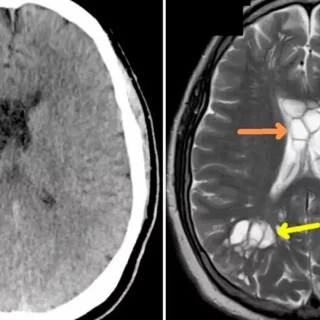

Un hombre con constantes migrañas descubre que tenía un parásito en el cerebro tras comer bacon poco hecho

El hombre sufría de migrañas agresivas y fue enviado a una exploración que mostró múltiples quistes en ambos hemisferios de su cerebro, que luego resultaron ser el resultado de una tenia del cerdo que había puesto huevos en su cerebro e irritaba el tejido debajo de su cráneo.